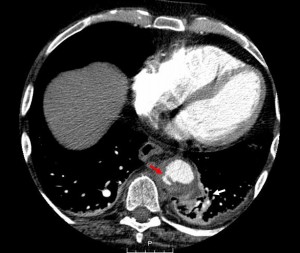

CT is the most common study to make the diagnosis. They are usually found incidentally. The CT should be performed without contrast and then with contrast. Intramural hematoma can actually be better visualized without contrast as blood is bright when the bleeding is acute. On the contrast exam, the hematoma may blend into the wall and seem like an atherosclerotic process.